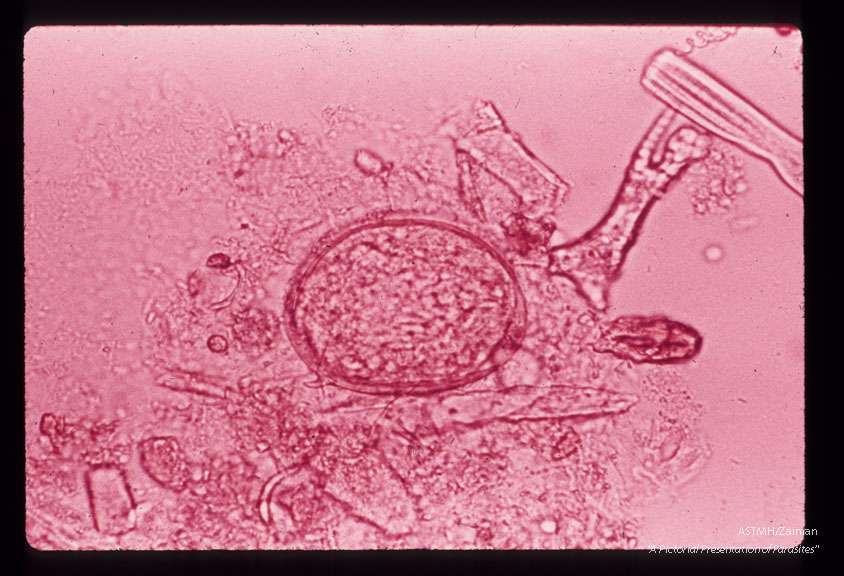

Egg in stool.

Schistosoma japonicum

Description: Egg in stool.